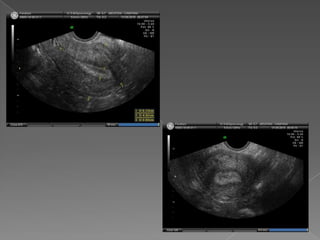

 Ecografía transabdominal

 Ecografía transvaginal

 Preparación : Se realiza con repleción vesical , desplaza

intestinos.

 Vejiga : ventana acústica , debe cubrir hasta el fondo

del útero

 Coloca los órganos en una distancia foca apropiada